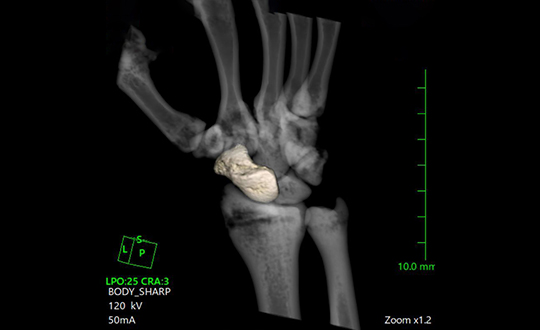

しずおか整形外科病院では、高画質・高速な撮影が可能な検査機器を取り入れております。また、高速な撮影により、検査時間の短縮や低被曝により患者様の負担を大幅に減らし、安心して検査を受けることができます。

1.80列マルチスライス(Canon)

短い時間で、体の中をくわしく撮影し、最先端の技術による被曝削減により安全に調べられる検査装置。